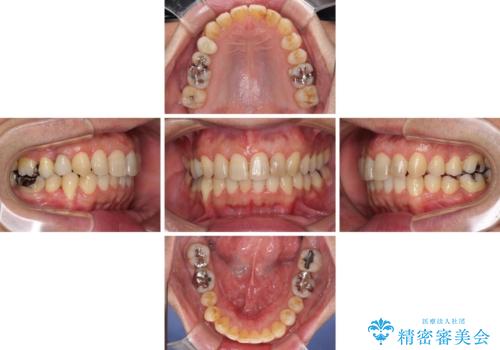

- 外に飛び出した側方の歯と、前歯のデコボコを気にして来院された患者様です。

IPR(歯と歯の間を削る)によってデコボコが解消するように設計し、インビザラインにより治療を行うこととしました。

治療途中で1年半以上通院されない時期があったため、後戻りが生じたことで治療期間が長くなってしまいました。

親知らずを抜去したことで、下顎のデコボコがきれいに解消されました。